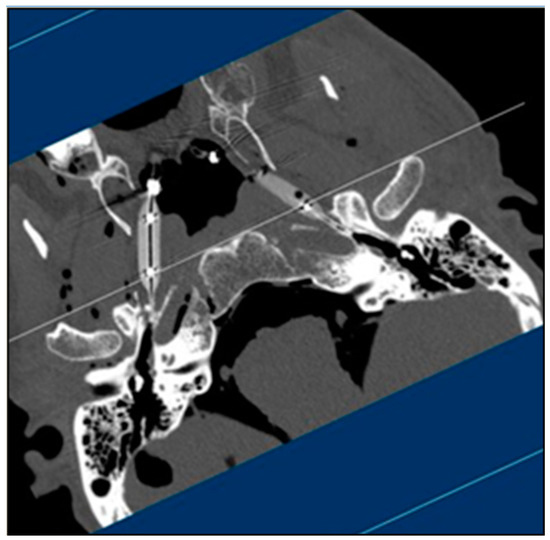

2.2. Experimental Protocol

2.3. Image Analysis